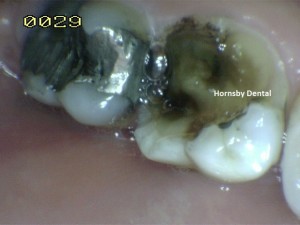

Hornsby Cosmetic Dentist - Amalgam Fracture (Dental Fillings and Restoration)

Before

Old silver/amalgam filling that appears to have no apparent problem, however our close examination reveals fracture-lines running across the tooth.

During

Deep recurrent decay accompanied by clearly visible fracture line. Amalgam restorations that have a high mercury content may behave like mercury in a thermometer – expands when termperature rises (hot food and drinks), and shrinks when cold. This can result in cracks of the tooth that is housing the amalgam.

After

Immediately after amalgam replacement, the tooth is fully functional and highly aesthetic. However given the deep crack that is present underneath the restoration, the tooth is best to have a crown to minimise the risk of tooth fracture.